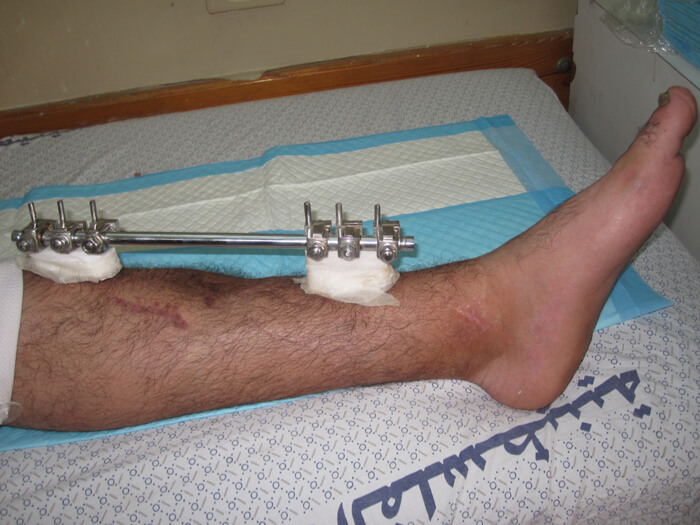

Figure 2a.

Figure 2b.

Figure 2c.

Figure 2a-c: Success story of patient treated by local surgeons: orthoplastic collaboration in country.

2a: 19-year-old male with a Gustilo IIIb middle 1/3rd tibia and fibular fracture, left leg

2b: Treated acutely with debridement and external fixator: x-ray at 2.5 months shows good alignment and signs of union.

2c: Fracture site was covered by a local fasciocutaneous flap within 11 days of the acute injury

Cases were screened and many had received timely orthoplastic care with excellent outcomes (Figure 2a-c). The local teams should be applauded that 70% of the open fractures received immediate, acute debridement and placement of an external fixator. The remaining 30%, with less serious open fractures, all received debridement and a fixator within three days of the injury. Forty percent of the fractures seen at screening needed no further orthopaedic intervention and 50% did not need plastic surgery interventions. Local education programmes clearly provide the best overseas aid possible. A UK teaching charity has supported local orthopaedic surgeons with training in limb reconstruction since 2009. This capacity building prior to this crisis saved many limbs.